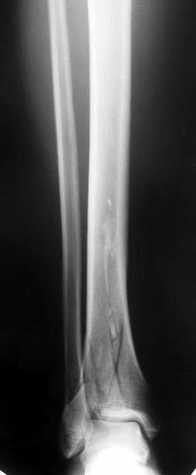

Глубокоуважаемые коллеги! Необходима ваша помощь.На консультацию обратился пациент 27 лет.

1,5 месяца назад при падении со скалы получил перелом пилона, лечился в районной больнице консервативно (циркулярная гипсовая повязка до средней 1/3 бедра). К нам попал только сегодня, сделали снимки и возник вопрос - делать ли что-то хирургически или уже пойти только на восстановительное лечение (продолжить иммобилизацию еще на 2-4 недели, потом разработка движений и т.п.)?Снимки прилагаю.

Уважаемые коллеги! Внутрисуставной перелом дистального конца б/б кости со смещением и подвывихом стопы должен был лечиться оперативно в раннем сроке.

По поводу обсуждаемого случая - 6-недельная фиксация такого перелома значительно увеличила шансы на артроз голеностопного сустава. Дальнейшая фиксация в гипсе практически сравняет эти шансы со 100%.